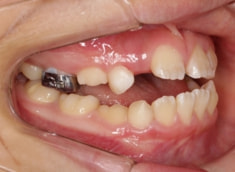

治療前

治療開始時